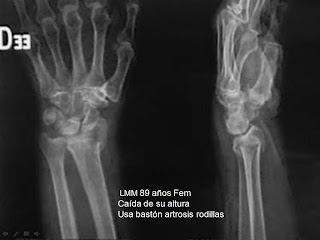

Una sexta parte de las fracturas atendidas en los servicios de urgencias corresponden a fracturas de radio distal. (1). Las fracturas de radio distal producidas por trauma de baja energía, entendiéndose como baja energía de acuerdo a la OMS traumas con la energía producida por una caída de su altura o menos, tienen una presentación bimodal: en la preadolescencia – adolescencia (2-3) y en la edad madura después de los 50 años.(4) En la primera etapa por mayor actividad física sin tener desarrollada toda la coordinación necesaria para evitar caídas y falta de mineralización del hueso en crecimiento. En la edad madura por aumento de caídas por pérdida de equilibrio, pérdida de visión, pérdida de reflejos y acondicionamiento físico. En las personas mayores ha también disminución de la masa ósea por edad, hábitos de vida y nutrición. (4-8)

Para resolver la fractura lo primero es determinar la “personalidad” y características de la fractura y del paciente; con la historia del trauma, forma en que ocurrió el accidente con sus detalles, los antecedentes personales y familiares especialmente de fracturas previas personales o familiares, hábitos y aspectos nutricionales, alérgicos y medicamentosos. El examen clínico y de imágenes que en algunas fracturas especialmente articulares requieren de exámenes especiales como la TAC.(18)